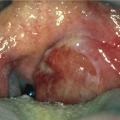

Rendu difficile par le trismus, l’examen endobuccal met en évidence une voussure unilatérale du pilier antérieur, associée à un œdème et un refoulement controlatéral de la luette (fig. 1).